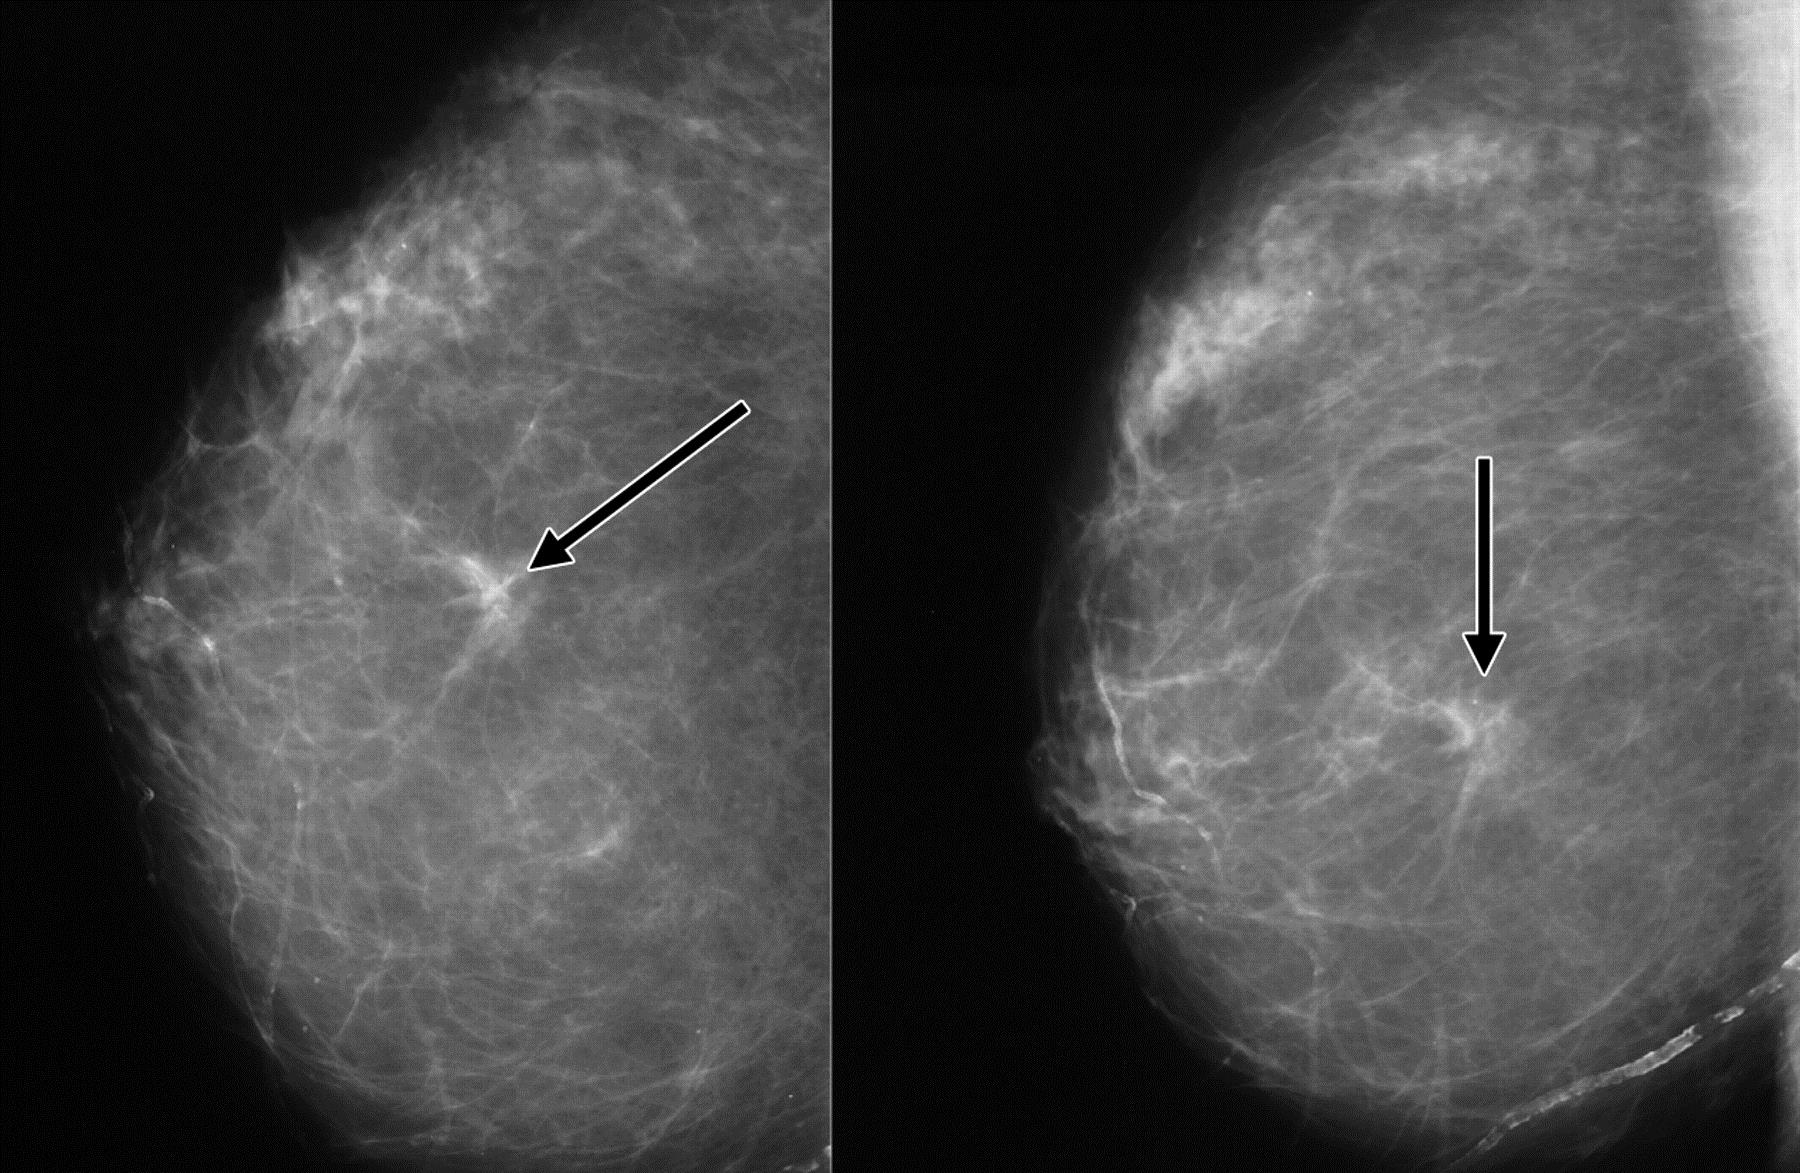

Фиброаденома молочной железы - доброкачественное образование, которое часто встречается у женщин. Оно может быть обнаружено при помощи различных методов диагностики, включая маммографию. Ниже представлены фотографии, помогающие понять, как выглядит данное заболевание.

Маммография и ее роль в диагностике фиброаденомы молочной железы

Маммография - это рентгенологическое исследование молочных желез. Оно позволяет выявить различные изменения в тканях, включая фиброаденому. На маммограммах можно увидеть структурные особенности опухоли и отследить ее динамику во времени.